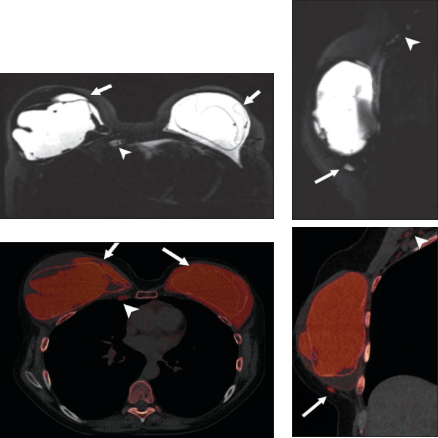

双能量硅图:硅胶假体破裂